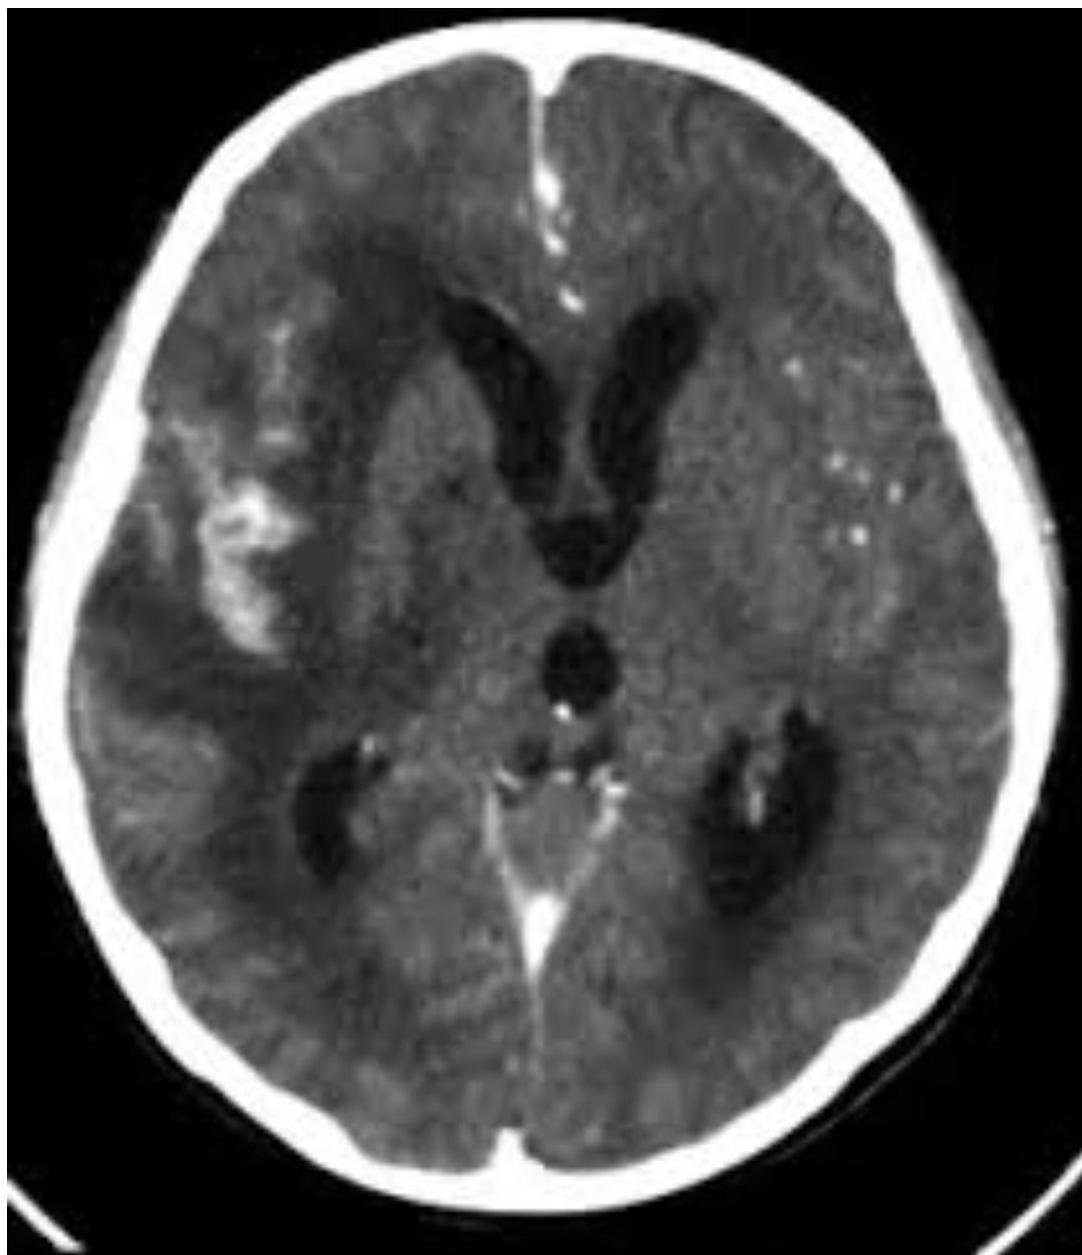

4. Tuberculous Meningitis

Most commonly occurs in children <5 years or immunocompromised patients, often within 6 months of primary infection.

- Pathophysiology: Tubercle bacilli seed the meninges during primary infection, replicate, and trigger inflammatory response leading to basilar meningitis.

- CT Findings: Hydrocephalus, cerebral edema, periventricular lucencies, infarctions.

- CNS Tuberculomas: Occur in 5% of CNS TB cases.